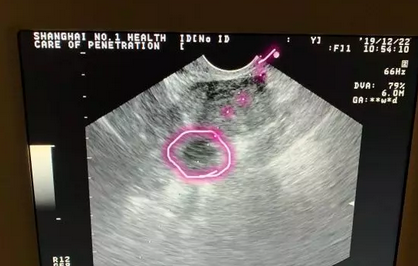

其实取卵手术是比较简单的,就是在阴道超声的监护下,用一根细长的取卵针经阴道扎入卵泡中,通过负压吸引将卵子取出体外的技术。

腹部穿刺取卵术进行中